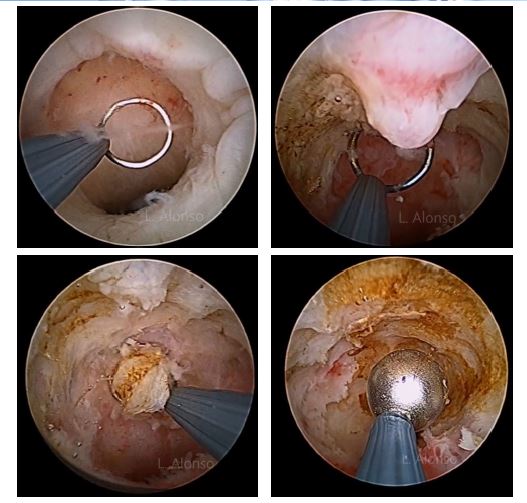

Se han propuesto diferentes opciones quirúrgicas para el tratamiento del istmocele. Por un lado, el tratamiento reparativo mediante corrección laparoscópica de la dehiscencia. Por otro lado, la corrección resectoscópica encaminada a mejorar los síntomas. Otras alternativas son, la corrección vía vaginal, así como el uso de tratamiento hormonal para reducir el sangrado menstrual. El tratamiento quirúrgico debería reservarse sólo para las pacientes sintomáticas con sangrado postmenstrual, dolor pélvico crónico o infertilidad secundaria. Las primeras dos opciones son las más comúnmente utilizadas, y la elección de una u otra está en relación con las condiciones anatómicas del istmocele.

La primera referencia al uso del resectoscopio en el tratamiento del istmocele fue de Fernández, quien realizó la resección del tejido fibrótico de la parte inferior de la cicatriz para facilitar el drenaje de la sangre menstrual coleccionada, mejorando así el sangrado postmenstrual. Desde entonces se han publicado múltiples artículos, y el tratamiento con resectoscopio se ha convertido en el abordaje que cuenta con más piblicaciones para el tratamiento de istmoceles sintomáticos.